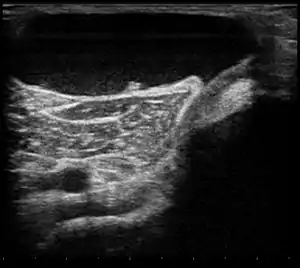

![]() | |

| Ultrasound image of Baker's cyst | |

Diagnosis is by examination. A Baker's cyst is easier to see from behind with the patient standing with knees fully extended. It is most easily palpated (felt) with the knee partially flexed. Diagnosis is confirmed by ultrasonography, although if needed and there is no suspicion of a popliteal artery aneurysm then aspiration of synovial fluid from the cyst may be undertaken with care. An MRI image can reveal presence of a Baker's cyst.